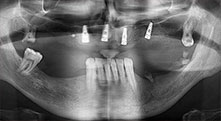

A 40-year-old patient with very poor residual dentition wanted an implant-based restoration. Because he is a smoker, a sinus lift in the maxilla with a fixed denture was contraindicated. A bar denture on four anterior implants was planned.

Piezomed B6

The alveolar ridge was split on both sides by piezo surgery (instrument: Piezomed B6). The implants were placed in the same procedure and the peri-implant bone was additionally built up using the GBR technique.

Implants

The four implants are in situ, as planned. The distal maxillary molars can still be used to fix the lined denture, which was introduced one month after implantation.